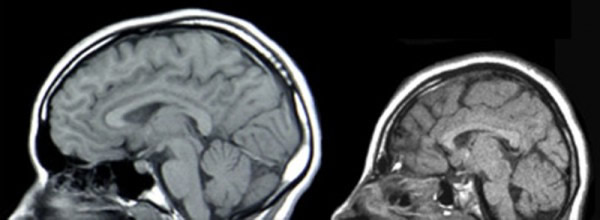

为了确定BRCA1在胚胎神经前体中的功能重要性,Inder Verma及其同事培育出了胚胎大脑缺乏BRCA1的转基因小鼠,结果发现这种突变小鼠的大脑的涉及认知、记忆、运动控制和感觉的几个片层结构——也就是新皮层、小脑、海马区以及嗅球——表现出了几种缺陷,包括细胞死亡和组织体积流失。这组作者发现实验删除肿瘤抑制基因p53能部分恢复缺乏BRCA1的小鼠受影响的大脑结构的正常片层化,这很可能是由于BRCA1的消失导致了p53调控的神经元前体细胞死亡。然而,只有在称为ATM的另一种信号传导蛋白被删除之后,BRCA1突变型小鼠的特定的神经元类型的细胞极性和中心体——参与细胞分裂的细胞器——的缺陷才被修正。

这些发现提示了一个模型,在这个模型中,BRCA1位于DNA修复和中心体功能的交汇处,这些功能是由p53和ATM参与的一个信号传导级联调控的,它很可能控制着大脑体积。研究人员说,BRCA1基因可能进化成了控制灵长类动物的大脑尺寸和结构。